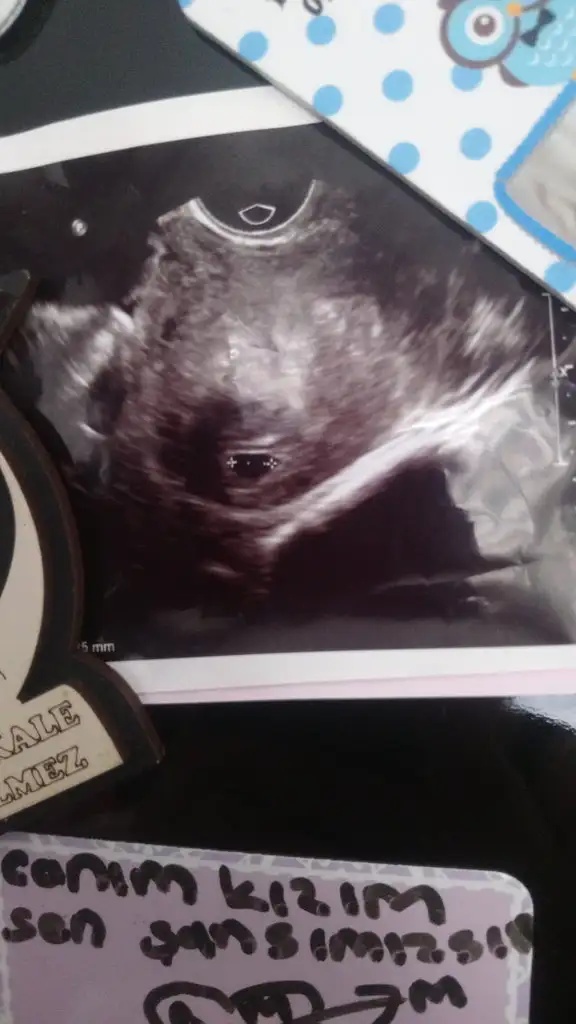

Hanımla merhaba, aranıza yeni katıldım bende sanırım nasipse şubat annesi olacam gibi sanki...6hafta 1günlüğüm sizler kaç haftasınıw bebeğinizi gördünüz mü?beraber ultrason resimleri paylaşalım..

Var mı bebisingm ultrason resmi paylaşabilir missm?benim bebisin i geçen hafta perşembe günü vAjimal ultrason ile 5hafta 2günlük iken keseyi gördük ve kenarda duruyordu, doktorum haftaya gel bakalım ne tarafa büyüyor dedi çok korkuyorum inanılmaz kötü birşey diyecek diye..bak benim ultrason resmi!

Eklentiler

• IMG-20190614-WA0003.webp

21,9 KB · Görüntüleme: 65